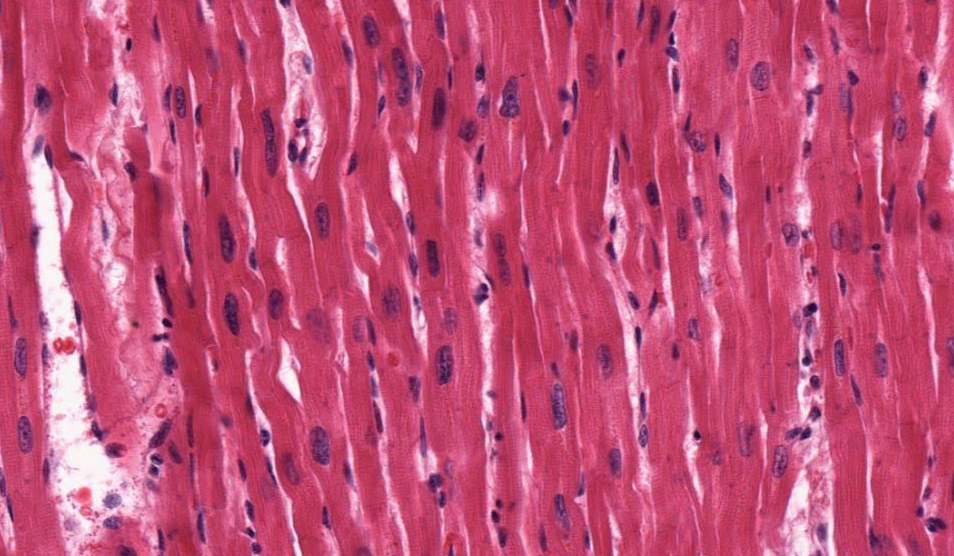

Tecido muscular (músculo cardíaco, em corte longitudinal).